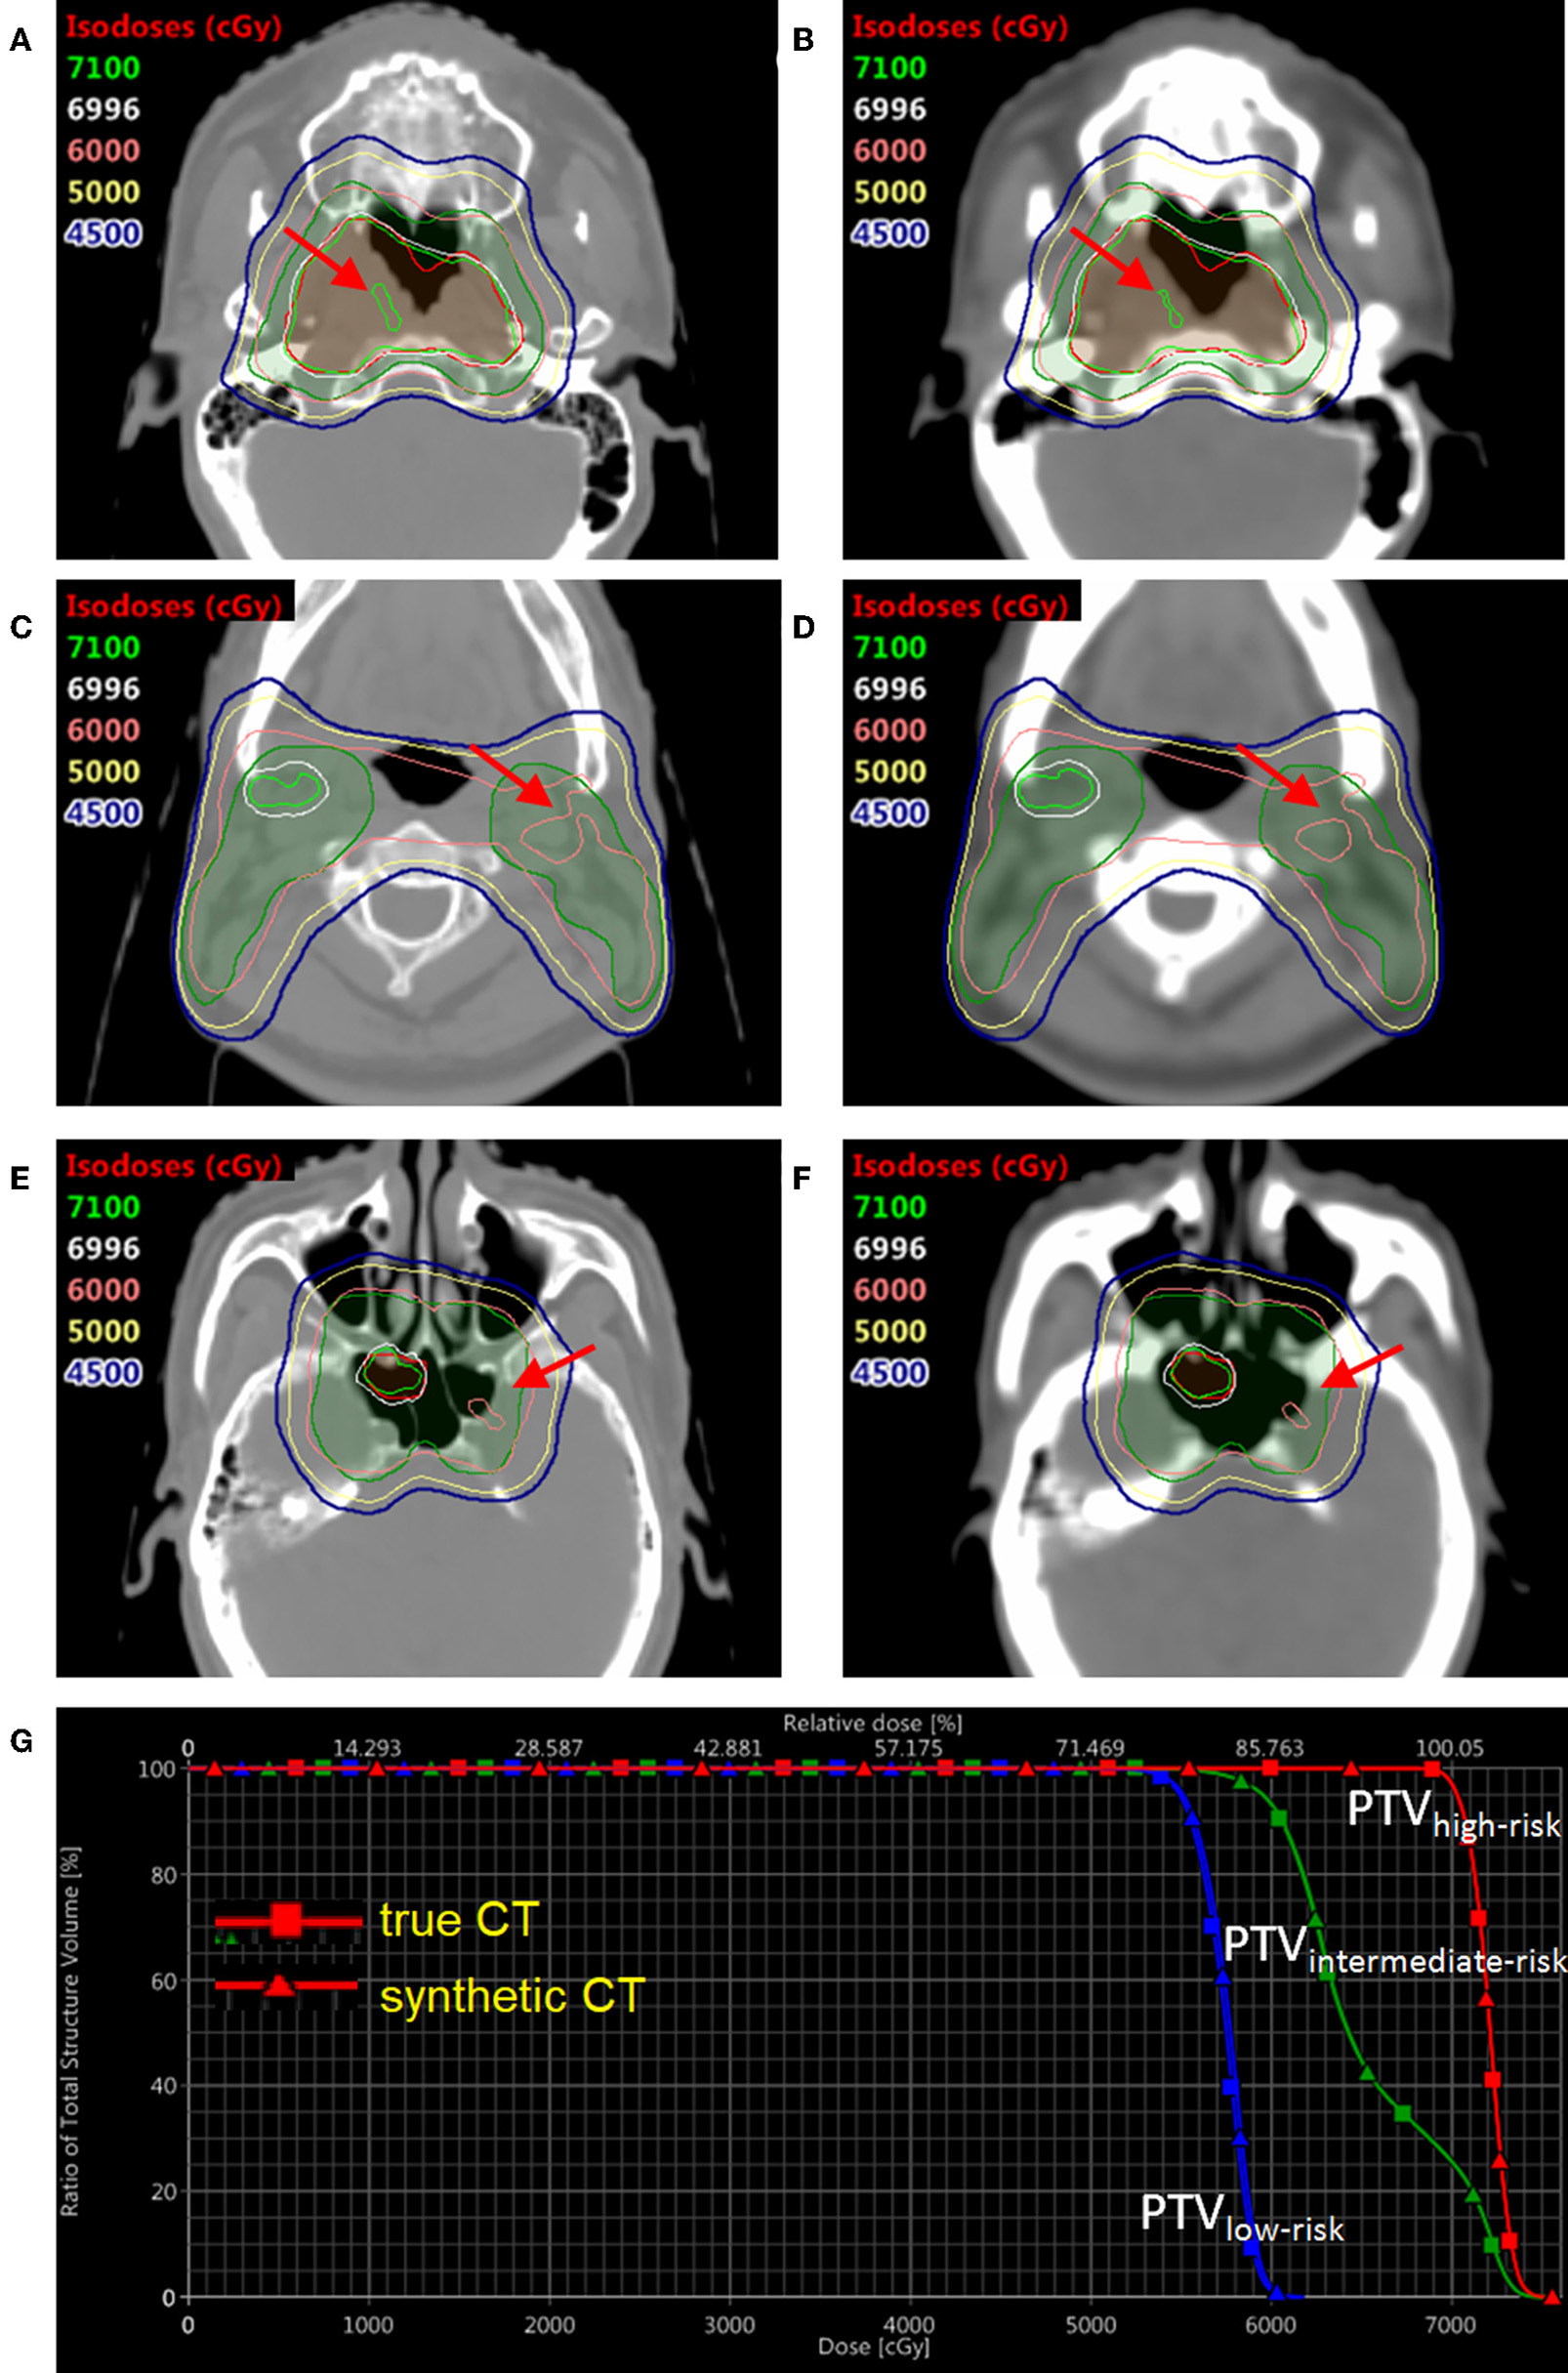

In order to compare the dose distribution using true vs. synthetic CT, one patient example was selected with the tumor in the sinus area and nearby fine bone structure (Figure 6). The mean HU value difference between true CT and sCT in the bone region was 191. The mean difference between true CT and sCT in the soft tissue region was 32. The treatment plan using the true CT was constructed with two full RapidArc in the Eclipse TPS v13.5 (Varian Medical Systems) and clinically approved by radiation oncologists. The dose distribution was subsequently recalculated based on sCT in the same treatment planning system. The three PTV regions, which were high-risk, intermediate-risk, and low-risk PTVs, as shown in DVH and isodose lines in Figure 6, had almost no difference between true and synthetic CT. For instance, the difference of D98% between the high-risk, intermediate-risk, and low-risk PTVs using true CT and sCT was <1%.

Figure 6. The dose distribution and DVH comparison between true CT and synthetic CT in an example NPC patient. Three slices of true CT are shown on the left (A,C,E); Three corresponding slices of synthetic CT are shown on the right (B,D,F). The DVH comparison based on true CT and synthetic CT is shown in (G). The translucent red region is high-risk PTV with prescription dose of 69.96 Gy; the translucent green region is intermediate-risk PTV with prescription dose of 60 Gy; the translucent blue region (not shown in axial views here) is low-risk PTV with prescription dose of 54.4 Gy. DVH with squares and triangles is based on true and synthetic CT, respectively.